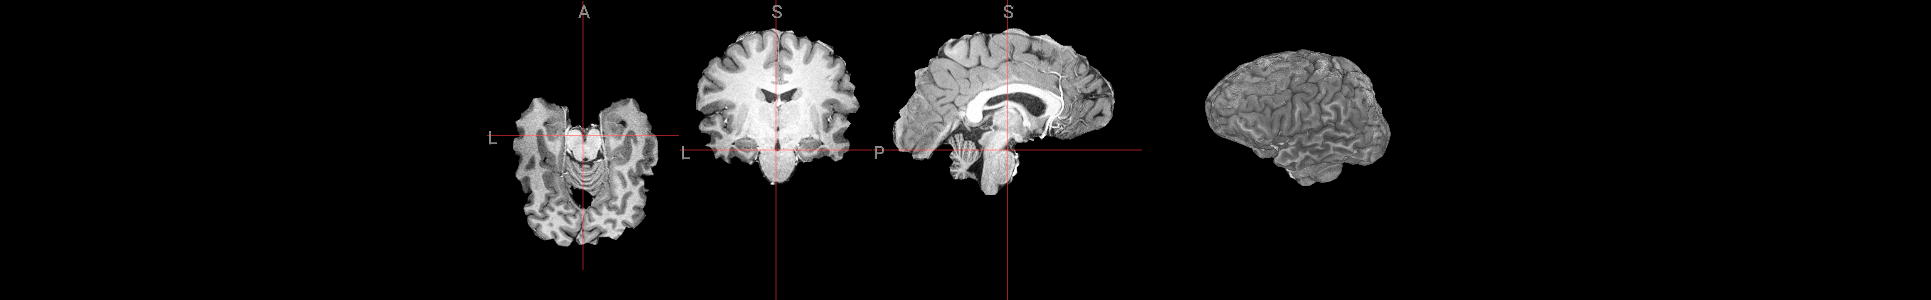

view_slices_3d(brain, slice_nbr=230, vmin=0, vmax=4000, title='Brain Extracted')

from ipyniivue import NiiVue

nv = NiiVue()

nv.load_volumes([{"path": "./sub-01_ses-01_7T_T1w_defaced_brain.nii.gz"}])

nv

from IPython.display import Image

Image(url='https://raw.githubusercontent.com/NeuroDesk/example-notebooks/refs/heads/main/books/images/sub-01_ses-01_7T_T1w_defaced_brain.png')